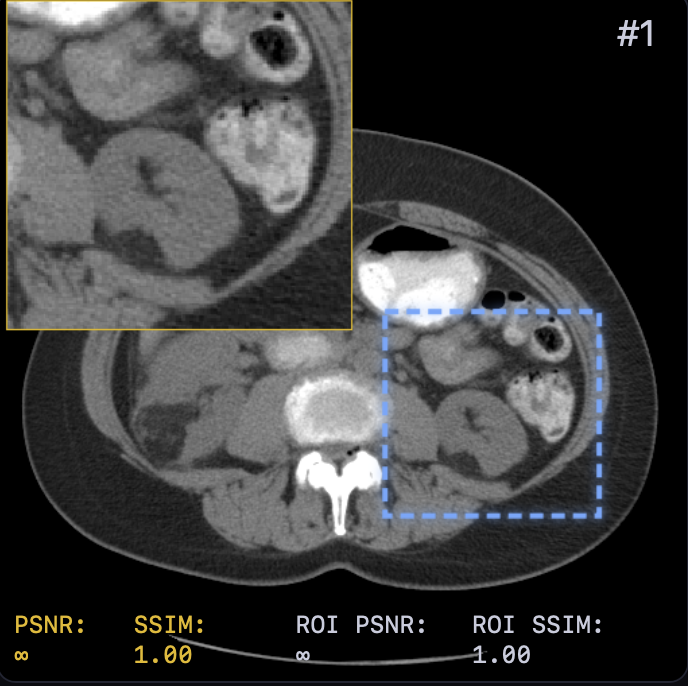

The reconstruction results are shown in Fig. 2. A zoomed-in region was extracted for a closer look with both PSNR and SSIM values attached. LTV preserves fine structures, such as vessel continuity, and reduces streak artifacts—critical for diagnostics—while avoiding the over-smoothing of TV or the anatomical inconsistencies of FBP+U-Net.